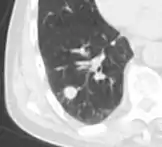

A lung nodule or pulmonary nodule is a relatively small focal density in the lung. A solitary pulmonary nodule (SPN) or coin lesion,[1] is a mass in the lung smaller than three centimeters in diameter. A pulmonary micronodule has a diameter of less than three millimetres.[2] There may also be multiple nodules.

One or more lung nodules can be an incidental finding found in up to 0.2% of chest X-rays[3] and around 1% of CT scans.[4]

The nodule most commonly represents a benign tumor such as a granuloma or hamartoma, but in around 20% of cases it represents a malignant cancer,[4] especially in older adults and smokers. Conversely, 10 to 20% of patients with lung cancer are diagnosed in this way.[4] If the patient has a history of smoking or the nodule is growing, the possibility of cancer may need to be excluded through further radiological studies and interventions, possibly including surgical resection. The prognosis depends on the underlying condition.